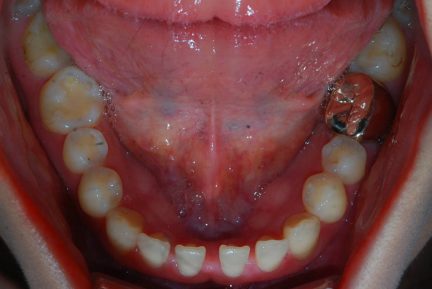

État initial

- Relation de Classe I obtenue

- Guidage fonctionnel des canines des deux côtés

- Surplomb et recouvrement normaux obtenus

- Arcades alignées et coordonnées

- Arcades harmonieuses obtenues